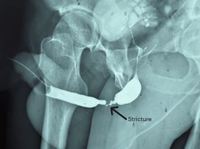

고압 케이블에 감전되는 사고를 당한 후, 수년이 지나 소변 길이 막혀버린 30대 남성의 사례가 보고됐다.모로코 물레이이스마일 군병원 비뇨기과 의료진에 따르면 33세 남성은 작업 중 금속 물체가 전선과 접촉하면서 감전 사고를 당했다. 동료들은 의식을 잃은 그를 즉시 병원으로 이송했다. 사고 당시 환자는 목, 다리, 등에 깊은 2~3도 화상을 입었지만 비뇨기계에는 직접적인 외상이 확인되지 않았다. 의식을 회복한 뒤 일시적인 배뇨 장애가 나타났지만 초기 치료를 통해 증상은 완화됐고, 화상 역시 흉터만 남긴 채 회복되면서 당시에는 큰 후유증이 없는 것으로 보였다.그러나 시간이 지나면서 환자에게 소변 줄기가 점점 가늘어지는 배뇨 장애가 나타나기 시작했다. 사고 발생 수년 뒤 진행된 정밀 검사에서 요도 내부 약 4cm 구간이 딱딱하게 굳어 좁아진 ‘요도 협착’이 발견됐다. 의료진은 환자의 입안 점막을 떼어 이식하는 구강 점막 이식 요도 성형술을 통해 손상된 부위를 재건했다. 수술 후 회복은 순조로웠으며, 6개월 추적 검사에서 정상적인 배뇨 흐름이 확인됐고, 협착 재발도 나타나지 않았다.요도 협착은 방광에서 체외로 소변을 배출하는 통로인 요도가 좁아지는 질환이다. 일반적으로 골반 골절이나 외상, 요도염, 장기간 도뇨관 삽입 등이 주요 원인으로 알려져 있으며 감전으로 인해 발생하는 경우는 매우 드문 것으로 보고된다. 전기화상은 전류가 신체 조직을 통과하면서 발생한다. 전류는 저항이 낮은 혈관과 신경을 따라 흐르기 때문에 피부 화상보다 내부 장기 손상이 더 심각할 수 있다. 또 전류가 다양한 조직을 통해 예측하기 어려운 경로로 흐르면서 유입·유출 지점에서 멀리 떨어진 부위에서도 조직 손상이 나타날 수 있다.특히, 요도 점막은 열 손상에 매우 민감하다. 고전압 전류에 잠깐 노출되는 것만으로도 주변 미세혈관이 손상돼 혈액 공급이 줄어드는 허혈성 손상이 발생할 수 있고, 심한 경우 손상이 점막을 넘어 해면체까지 확장돼 섬유화되면서 요도 협착으로 이어질 수 있다.의료진은 “전기 손상은 겉으로 보이는 화상보다 내부 조직 손상이 더 심각할 수 있는 외상”이라며 “감전 사고 이후 시간이 지난 뒤에도 배뇨 장애 같은 증상이 나타난다면 요도 협착 가능성을 고려해야 한다”고 말했다.이 사례는 ‘큐레우스’ 저널에 지난 15일 게재됐다.